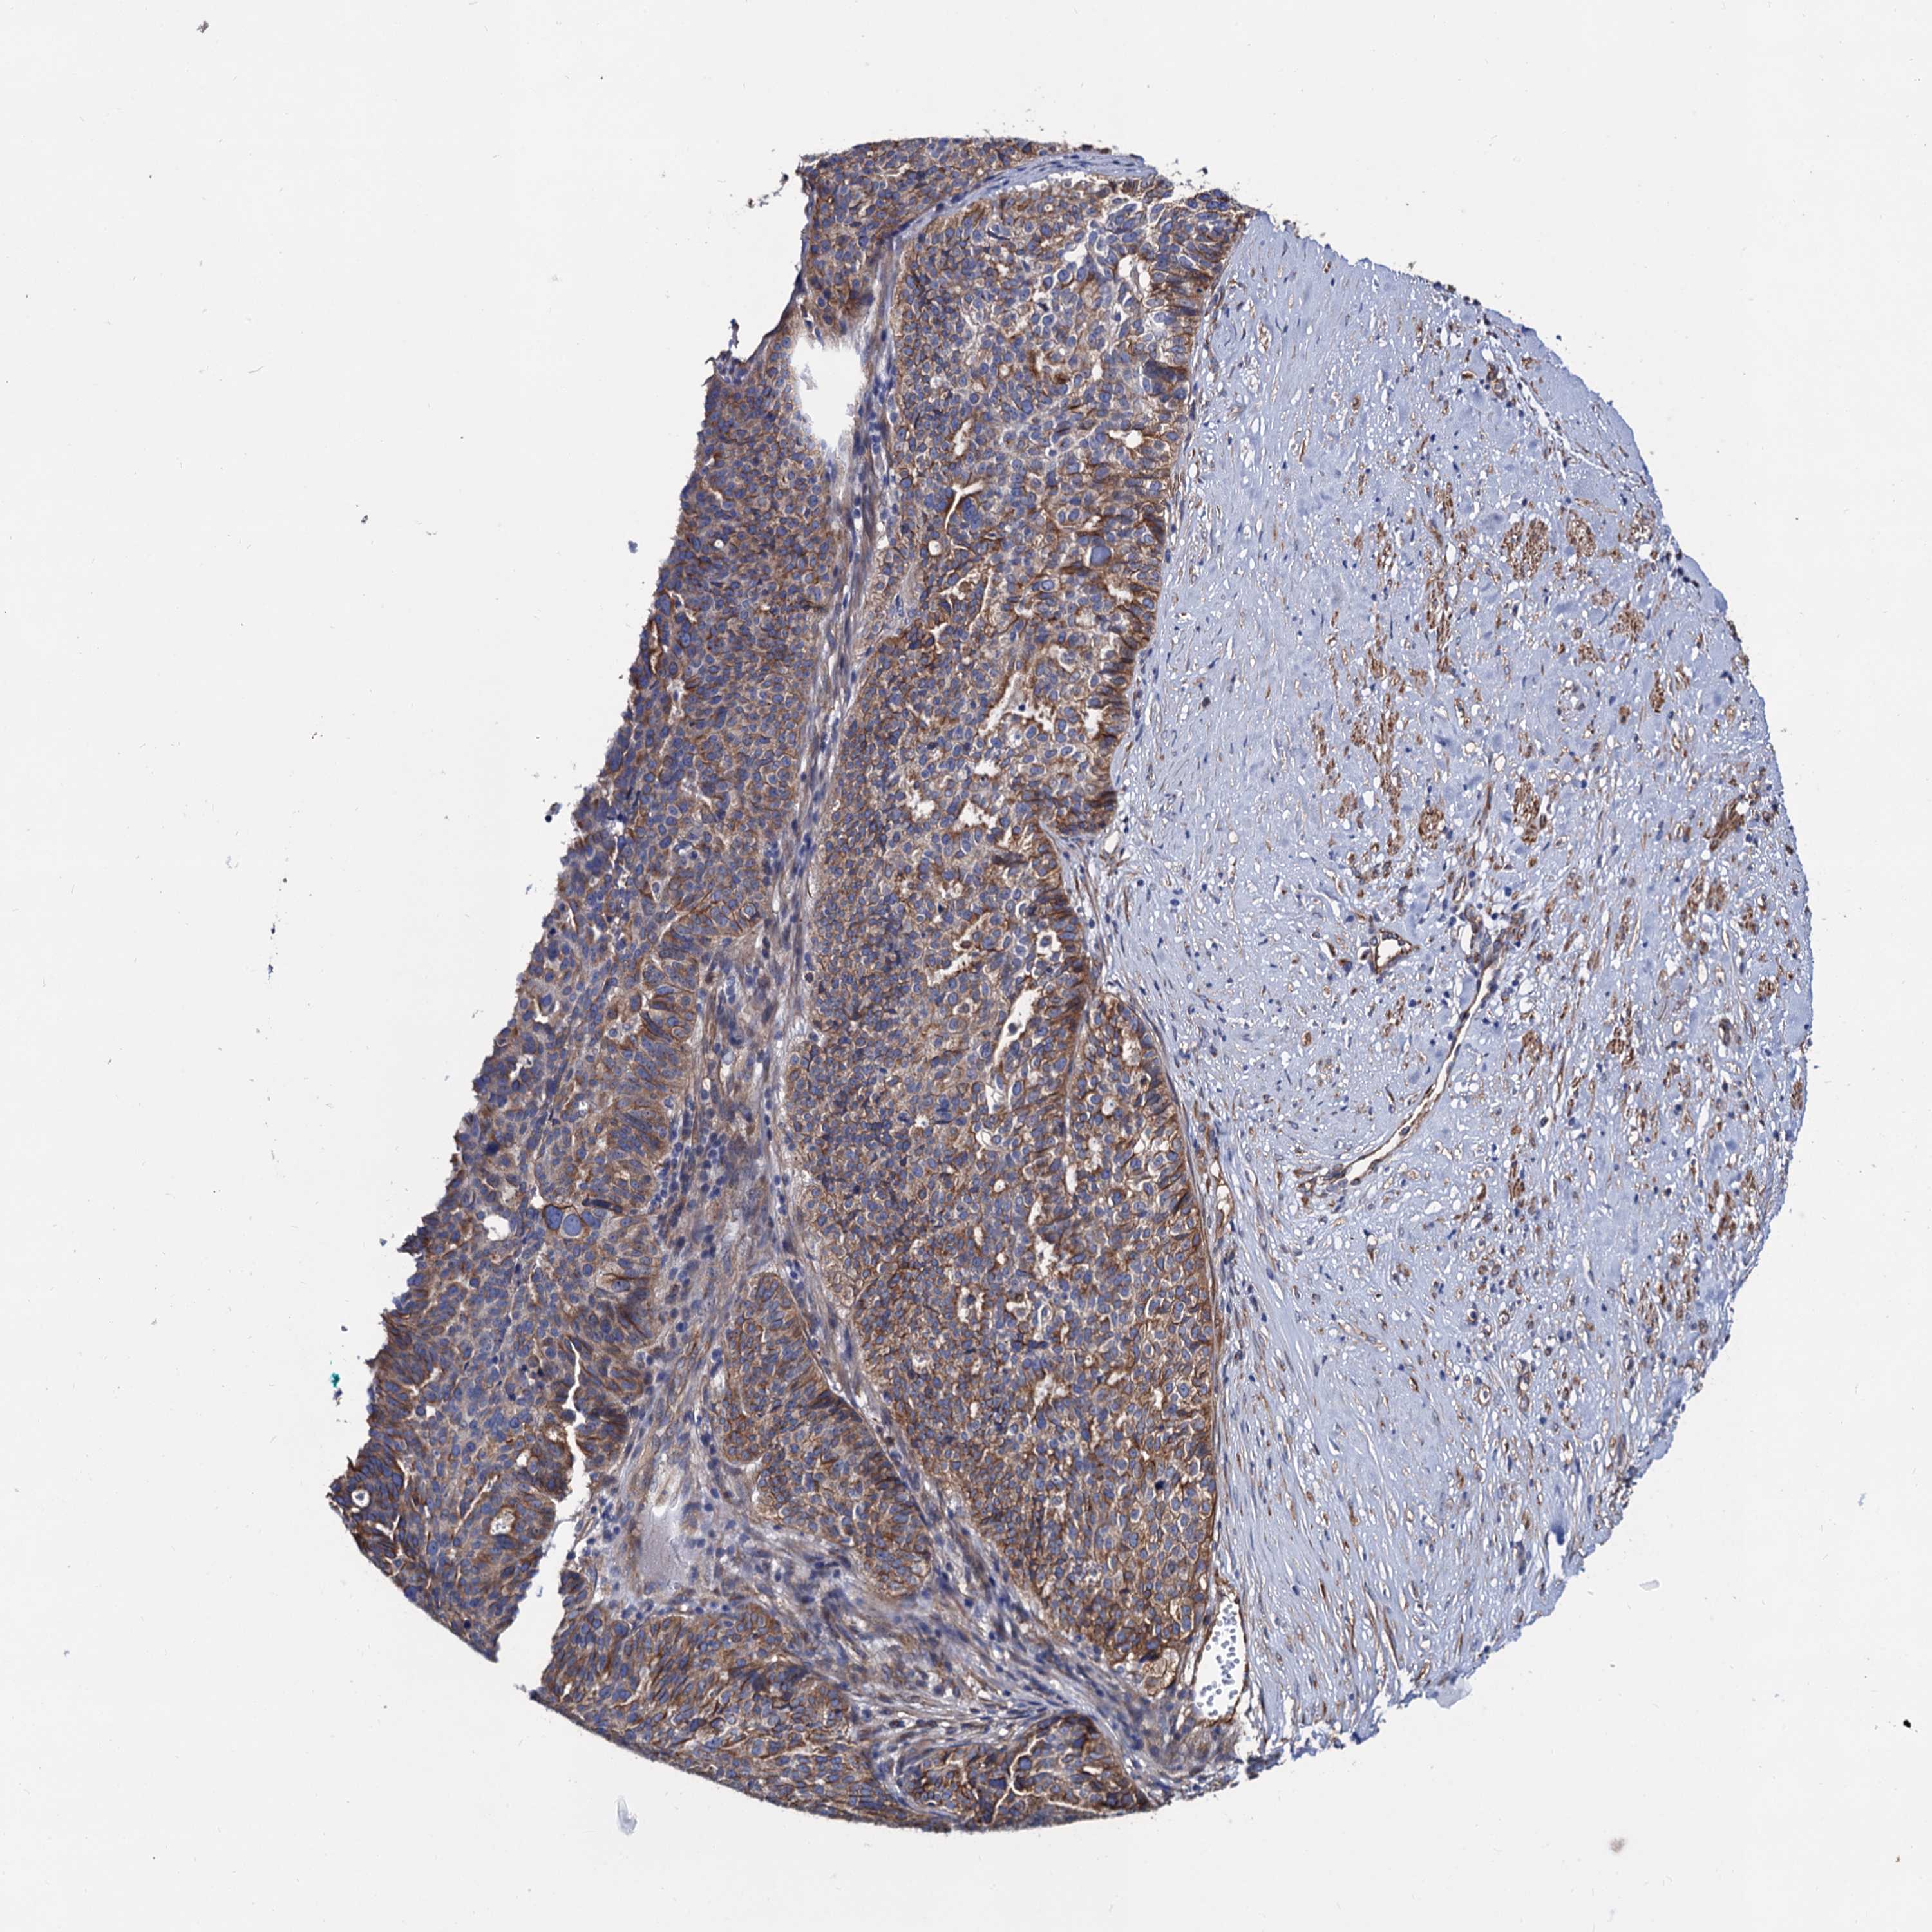

OVARIAN CANCER - Protein expressioni

A mouse-over function shows sample information and annotation data. Click on an image to view it in a full screen mode. Samples can be filtered based on level of antibody staining by selecting one or several of the following categories: high, medium, low and not detected. The assay and annotation is described here.

Note that samples used for immunohistochemistry by the Human Protein Atlas do not correspond to samples in the TCGA dataset.

Antibody stainingi

Antibody staining in the annotated cell types in the current human tissue is reported as not detected, low, medium, or high, based on conventional immunohistochemistry profiling in selected tissues. This score is based on the combination of the staining intensity and fraction of stained cells.

Each image is clickable and will lead to virtual microscopy that enables deeper exploration of all samples and also displays staining intensity scores, fraction scores and subcellular localization as well as patient and tissue information for each sample.

Antibody HPA040234

Staining

High

Medium

Low

Not detected

Intensity

Strong

Moderate

Weak

Negative

Quantity

>75%

75%-25%

<25%

None

Location

Nuclear

Cytoplasmic/membranous

Cytoplasmic/membranous,nuclear

Cystadenocarcinoma, serous, NOS

Carcinoma, endometroid

Cystadenocarcinoma, mucinous, NOS

Carcinoma, NOS